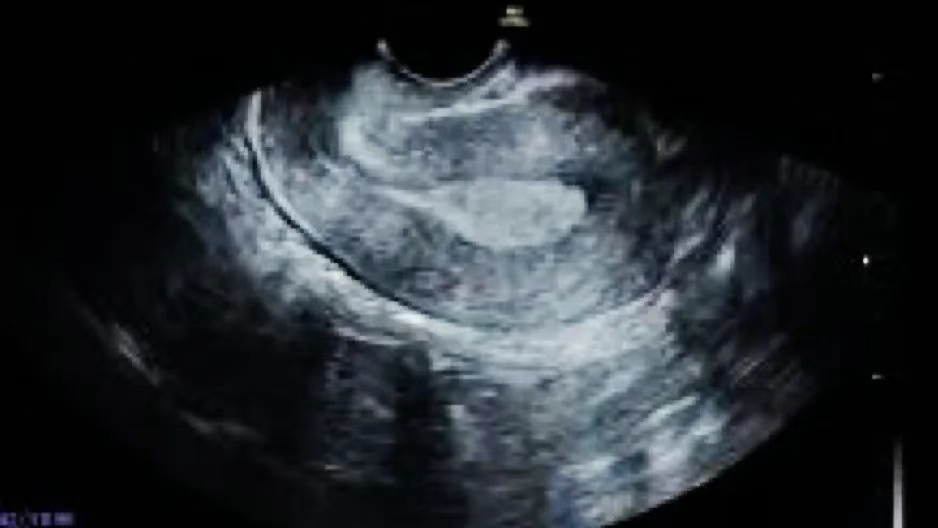

常见于月经第6-10天(月经基本结束),内膜厚度约为4-9mm,超声下能看见清晰的三条线,构成“三线征”(宫腔线、前后壁内膜线清晰)。

此阶段在雌激素的作用下,内膜细胞不断增殖、分化,腺体增长弯曲,间质逐渐水肿,使得内膜逐渐增厚且结构清晰。

美国试管专家指出,A 型内膜的这种结构特点,有利于胚胎在其中找到合适的位置 “扎根”,其良好的血液供应和营养环境,能够为胚胎提供充足的氧气和养分,是最适合胚胎着床的内膜类型之一。